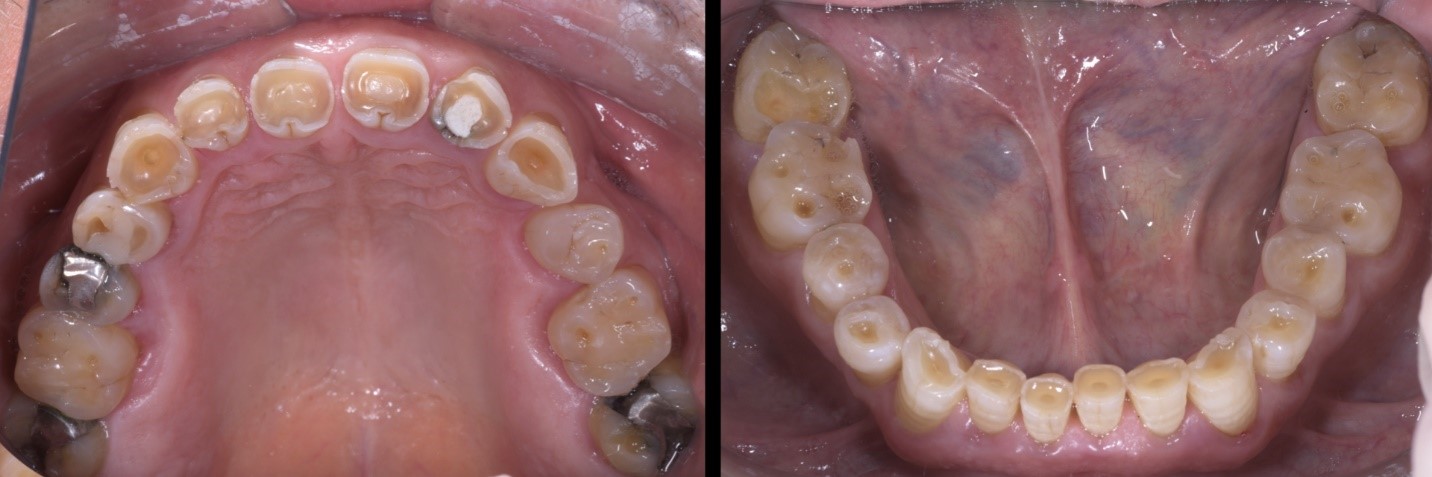

Fig. 4a e 4b

Gli elementi dentali coinvolti da lesioni cariose vengono precedentemente restaurati con materiale composito, mediante l’utilizzo di anelli e matrici Garrison Dental Composi-Tight 3D-Fusion.

L’apertura degli spazi interprossimali in maniera minimamente invasiva è agevolata dall’uso delle strip abrasive Garrison Dental FitSrip, montate su apposito manico di supporto.